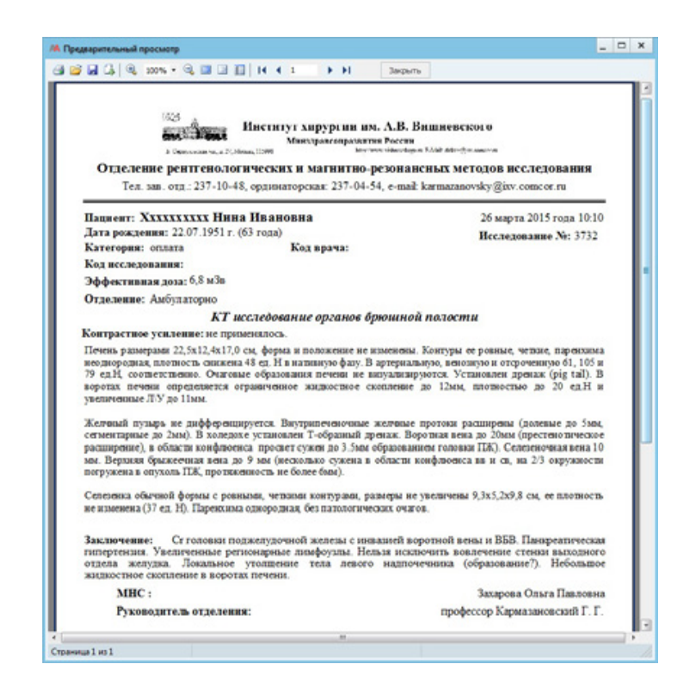

- Описание и отчетность: Удобные рабочие станции для врачей-рентгенологов с шаблонами протоколов, голосовым вводом и поддержкой нормативных форм.

- Доступ к результатам: Быстрая выдача заключений пациентам и предоставление удаленного доступа к снимкам и протоколам лечащим врачам через веб-клиент или интеграцию с МИС.